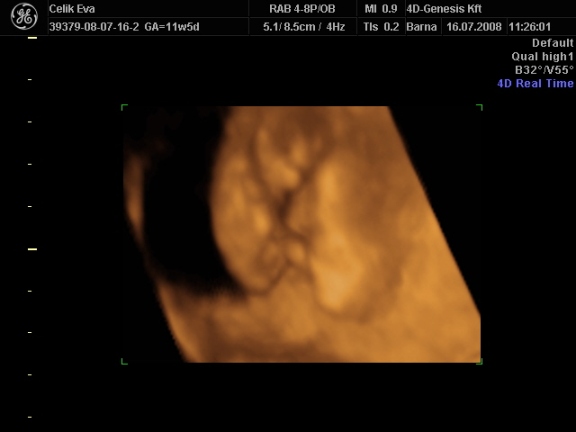

a képek:

3d-s babafotók:

ha megfürödtek a fiuk rakok fel 2d-s fütyis képeket is,meg egyet amin olyan édes arcocskája van :lol:

2d-s

ezen olyan aranyos baba arca van :lol: Kép